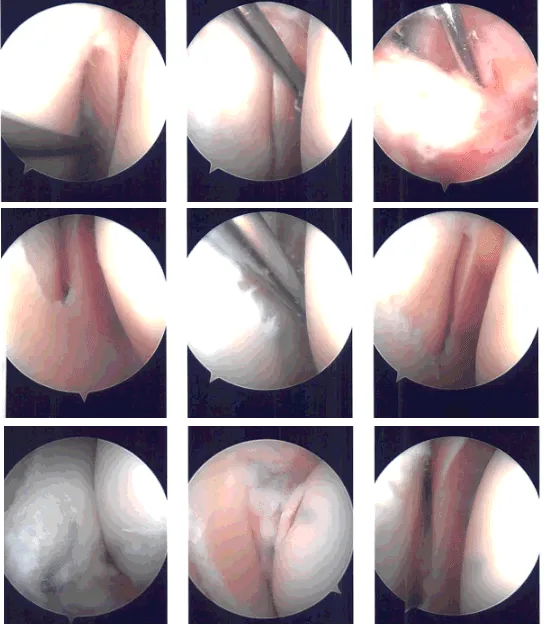

Lateral entry portal was made. Arthroscope was introduced. There were grade 2 to grade 3 osteoarthritic changes on the posterior surface of the patella on the lateral facet. There were loose cartilage fragments in the medial gutter. Examination of the medial compartment showed medial meniscus tear.

The medical entry portal was made using a spinal needle. A shaver was used to clear the joint as well as the meniscus. Biters were used sequentially to do the medial meniscectomy in the mid portion of the body.

The posterior root of the meniscus was found to be loose and on further examination, it was found that it was torn from the whole knee attachment. A decision was done to do a repair of the meniscal root. Examination of the Intercondylar notch showed the ACL was intact.

Examination of the lateral tibiofemoral compartment showed fraying and tearing of the medial edge of the lateral meniscus, which was cleaned using the biter as well as the shaver. Examination of the patellofemoral compartment showed grade 3 to grade 4 osteoarthritic changes of the lateral trochlea as well as the lateral facet of the patella.

Chondroplasty was performed. The scope was entered from the medical portal to re-confirm the findings. Again, the scope was entered from the lateral portal and repair for the medial meniscus root was planned.

The Arthrex jig was used to make an entry portal from the medial tibial condyle into the posterior plateau. The FlipCutter was used to make a depression for the root to insert and abrade the bone intraarticularly. Knee Scorpion was used to pass two FiberLinks.

The FiberLinks were sutured through the canal using suture lasso. The sutures were put in tension and fixed to the tibia using SwiveLock #4.75. Final pictures were again taken and saved.

The knee was thoroughly irrigated. Microfracture of intertrochlear notch was done using the chondral pick set. Fat pad could be seen coming out of the microfracture. The knee was irrigated and drained. The knee was closed using # 4-0 nylon. A 30 cc of Naropin was injected into the knee.

Intraoperative Arthroscopy Images